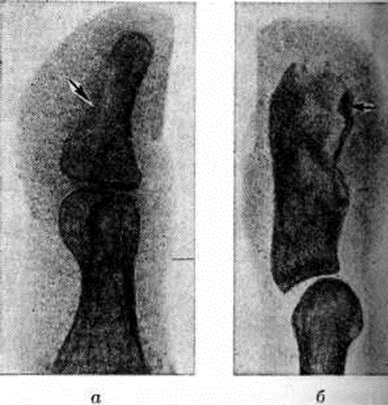

При костном панариции уже к концу 1-й недели болезни на рентгенограммах отмечается неравномерное просветление — реактивный остеопороз поражённой части фаланги вплоть до почти полного исчезновения структуры этой части фаланги при дальнейшем развитии Панариций (рисунок 6, а). По затихании воспаления очертания и структура фаланги восстанавливаются через 3—5 недель Ошибочное толкование этого просветления фаланги как некроза может привести к неоправданной резекции или даже экзартикуляции жизнеспособной фаланги. В отличие от описанной картины некротизированная часть фаланги, лишённая кровоснабжения, сохраняет на рентгенограммах тень нормальной интенсивности; образовавшийся секвестр часто смещается (рисунок 6, б). При интактности смежного сустава суставная щель и Подхрящевые корковые слои сохраняются. При осложнении костного Панариций гнойным артритом на рентгенограммах помимо остеопороза наблюдается прогрессирующее сужение суставной полости (вследствие хондролиза суставных хрящей), неровность и нечёткость контуров суставных концов (рисунок 7, а). Иногда гнойный артрит может осложниться дистензионным вывихом или подвывихом фаланги (рисунок 7, б).

Суставной Панариций ведёт к анкилозу; при этом на рентгенограмме исчезают корковые слои суставных концов и суставная полость, на месте которой костно-трабекулярная структура переходит из одной кости в другую. При активно и длительно текущем костном или суставном Панариций может наблюдаться просветление всех смежных костей кисти (главным образом суставных концов костей), то есть регионарный остеопороз. При костном Панариций дистальной фаланги на рентгенограммах отсутствует оссифицирующий периостит вследствие малой активности здесь камбиального, остеогенного слоя надкостницы.